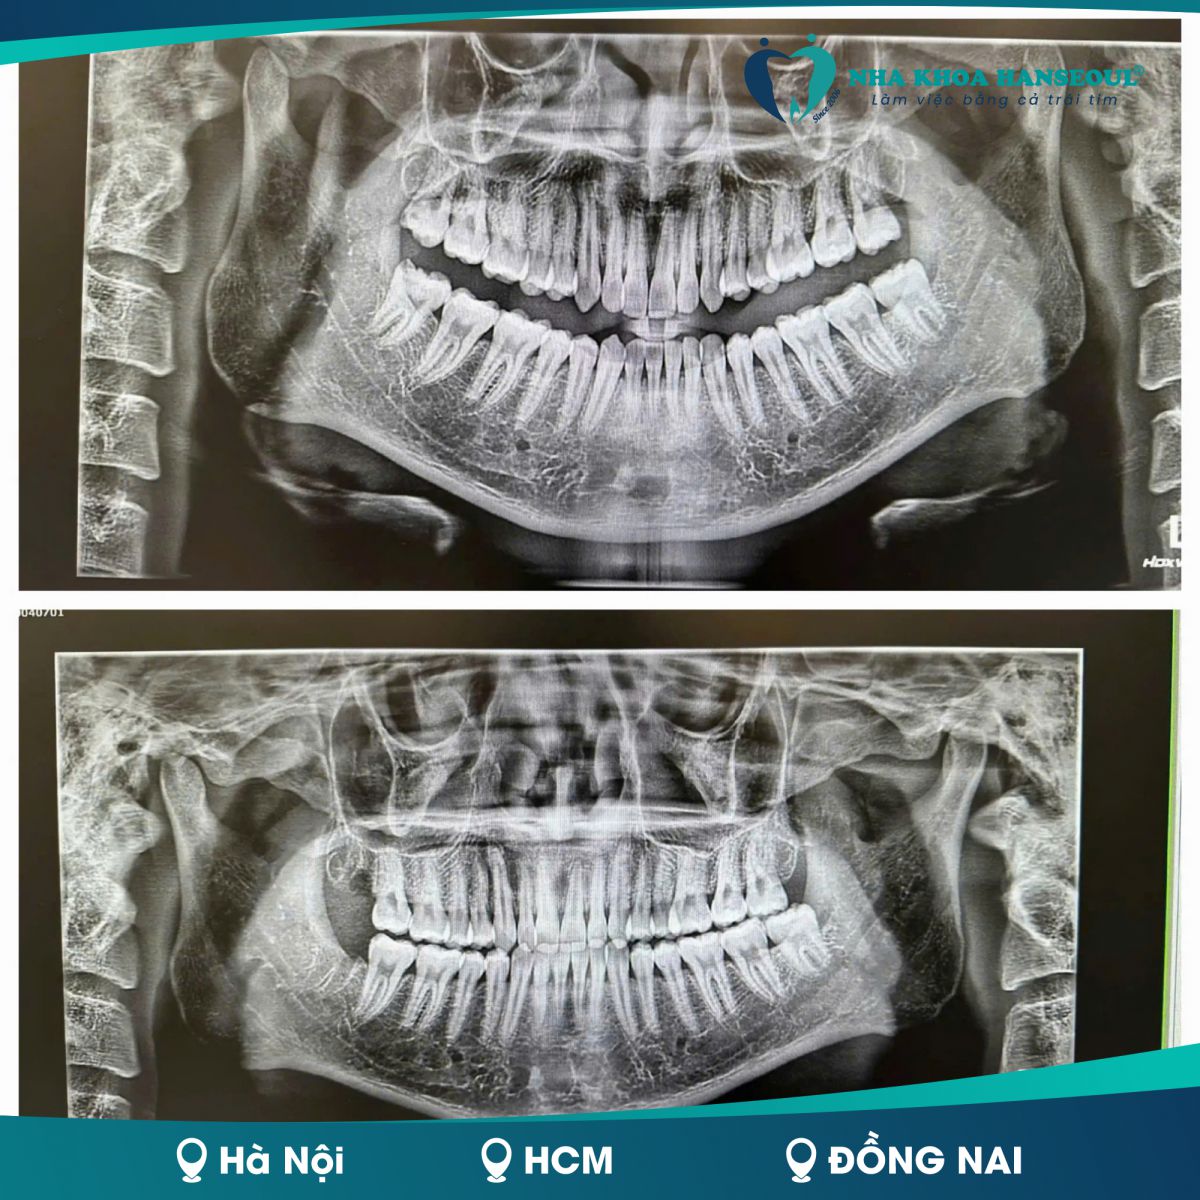

Thông qua phim X-quang toàn cảnh, bác sĩ sẽ xác định chính xác vị trí và hướng mọc của răng để chỉ định phẫu thuật. Việc nhổ răng ngầm cần được thực hiện bởi bác sĩ giàu kinh nghiệm với trang thiết bị hiện đại để tránh tổn thương dây thần kinh.